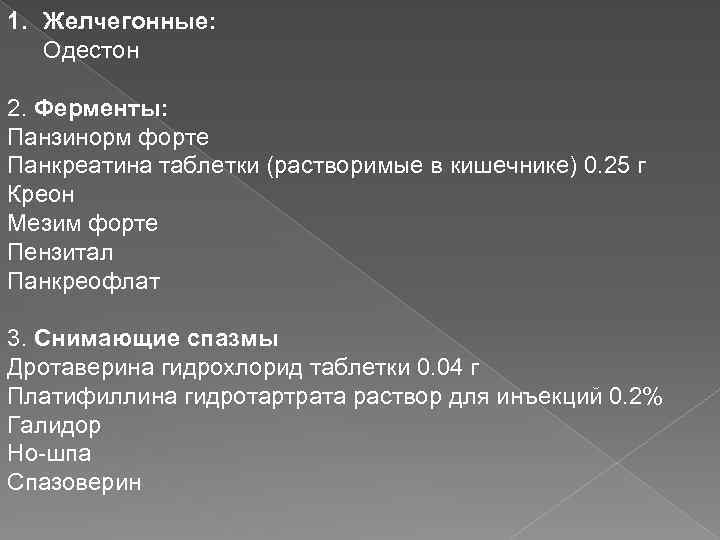

1. Желчегонные: Одестон 2. Ферменты: Панзинорм форте Панкреатина таблетки (растворимые в кишечнике) 0. 25 г Креон Мезим форте Пензитал Панкреофлат 3. Снимающие спазмы Дротаверина гидрохлорид таблетки 0. 04 г Платифиллина гидротартрата раствор для инъекций 0. 2% Галидор Но-шпа Спазоверин

1. Желчегонные: Одестон 2. Ферменты: Панзинорм форте Панкреатина таблетки (растворимые в кишечнике) 0. 25 г Креон Мезим форте Пензитал Панкреофлат 3. Снимающие спазмы Дротаверина гидрохлорид таблетки 0. 04 г Платифиллина гидротартрата раствор для инъекций 0. 2% Галидор Но-шпа Спазоверин